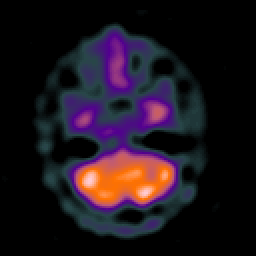

Huntington's Chorea, MR -- Slice #3

[Home][Help][Clinical] Slice 3